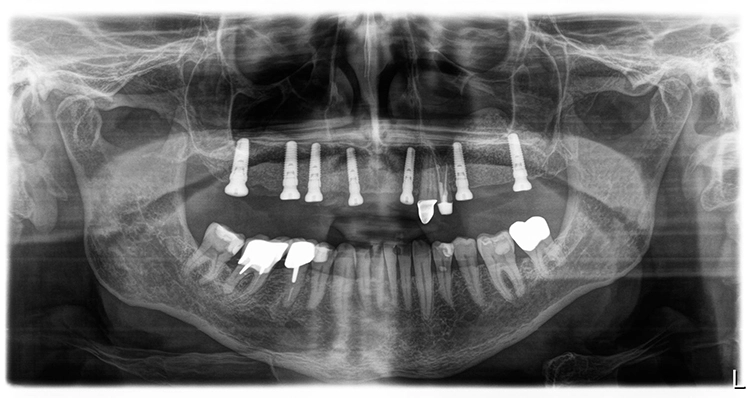

Nach einer – aufgrund eines Campingurlaubs von sechs auf acht Monaten – verlängerten Heilphase konnte der Patient implantiert werden. In der Röntgenkontrollaufnahme zeigten sich stabile knöcherne Strukturen in den augmentierten Bereichen des Sinus. Die Insertionen erfolgte gemäß Protokoll frei Hand auf Grundlage der DVT-Aufnahme und orientiert an der alten Teleskopprothese.

Die Freilegung der Implantate erfolgte mit minimalinvasiver Stichinzision. Die Verschlussschrauben wurden entfernt und Gingivaformer eingesetzt, um das Weichgewebe auszuformen. Die ursprüngliche Teleskopprothese wurde im Bereich der Gingivaformer ausgeschliffen und mit einer Gaumenplatte erweitert.

So konnte sie als Interimsversorgung, verankert auf den Zähnen 23 und 24, über den Gingivaformern als Interimsersatz genutzt werden und sich das Weichgewebe unbelastet um die Implantate herum ausformen. Einige Wochen später – wiederum verzögert durch einen Campingaufenthalt – konnte auf dem mittlerweile befestigten und stabilen Weichgewebe für die Herstellung der definitiven Restaurationen abgeformt werden. Hier ist von Vorteil, dass die Conelog Abformpfosten nicht in den Konus des Implantats eingreifen, sondern auf der Implantatschulter aufliegen, wodurch ein Höhenversatz bei der Abformung vermieden wird.

Zeitgleich mit der Freilegung wurde Zahn 13 extrahiert. Nach sorgfältiger Exkochleation wurde die unversehrte Alveole im Sinne einer Socket Preservation mit bovinem Knochenersatzmaterial (MinerOss X) verfüllt und mit einer porcinen Kollagenmembran (MemLok Pliable) abgedeckt. Damit lässt sich ein postoperativer Gewebeabbau und eine Einschränkung der Weichgewebeästhetik unter einem Brückenglied weitgehend vermeiden: Die Socket Preservation mit bovinem Knochenmineral und porciner Kollagenmembran schränkt die horizontale und vertikale Knochenresorption im Vergleich zur alleinigen Extraktion erheblich ein (Abb. 19 und 20) [1,6,9].